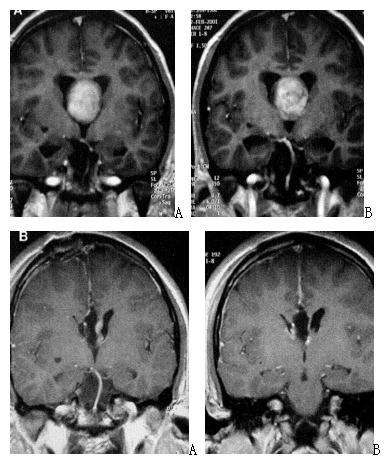

图3. 六例实性侵袭第三脑室颅咽管瘤手术前、后的增强磁共振影像以及手术中截图,提示肿瘤全部切除,可以看到第三脑室后壁、室间孔和中脑导水管上口。